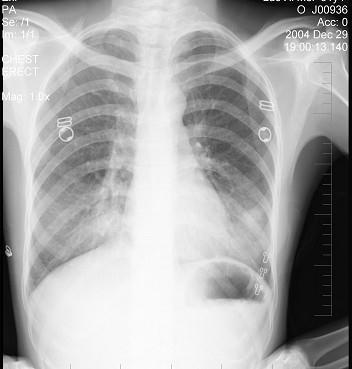

女性患者,31岁,咳嗽发热1周,胸片检查如图,最明确的诊断是 ( )A.两肺结核B.两肺炎症C.两侧胸膜炎D.两肺不张E.双侧支气管扩张

问题 女性患者,31岁,咳嗽发热1周,胸片检查如图,最明确的诊断是 ( )

选项 A.两肺结核 B.两肺炎症 C.两侧胸膜炎 D.两肺不张 E.双侧支气管扩张

答案 B